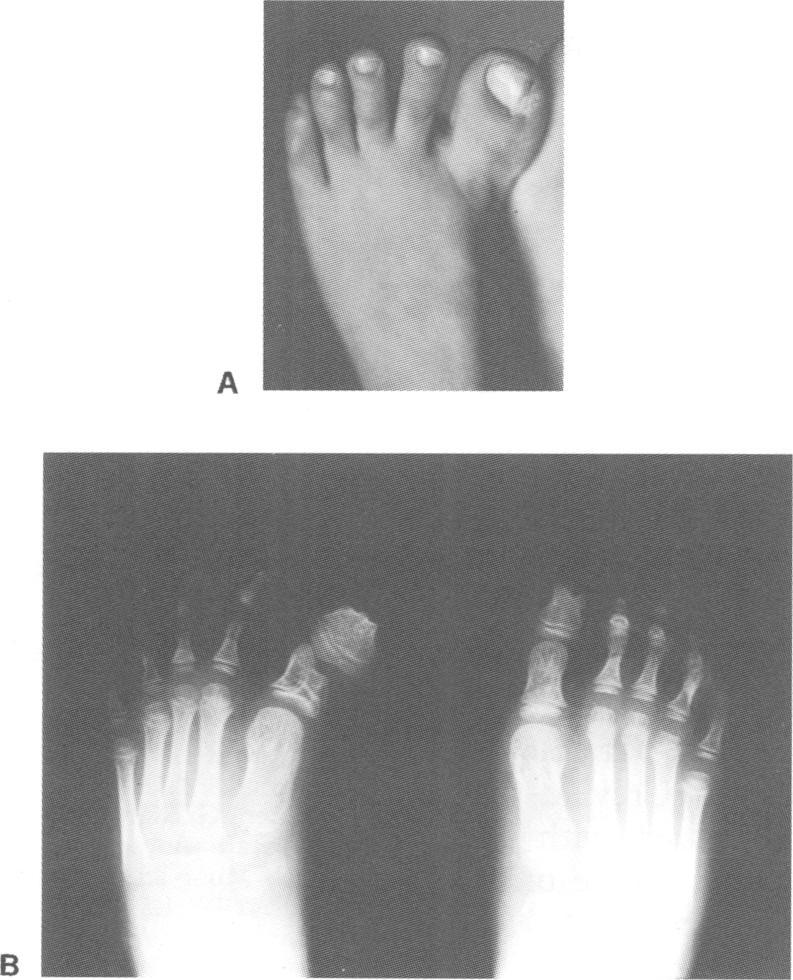

We report on a patient with a constellation of anomalies including hamartomas of the tongue, polysyndactyly, and atrioventricular canal. A similar association has been previously described by Orstavik et al in two sibs. The clinical spectrum of the oralfacial-digital syndrome (OFDS) type II includes all these features. In particular, congenital heart defect, mainly atrioventricular canal, has been described in a few cases. It has been previously suggested that these latter patients may be affected by a variant of OFDS type II. We propose to distinguish this orocardiodigital variant and point out the association of the syndrome with atrioventricular canal.

我们报告了一名患有一系列异常症状的患者,这些异常包括舌错构瘤、多指(趾)畸形和房室管畸形。此前,奥尔斯塔维克等人曾在两名同胞中描述过类似的关联。II型口面指综合征(OFDS)的临床症状包括所有这些特征。特别是,少数病例中曾描述过先天性心脏缺陷,主要是房室管畸形。此前有人提出,这些患者可能受到II型OFDS变异型的影响。我们建议区分这种口心指变异型,并指出该综合征与房室管的关联。